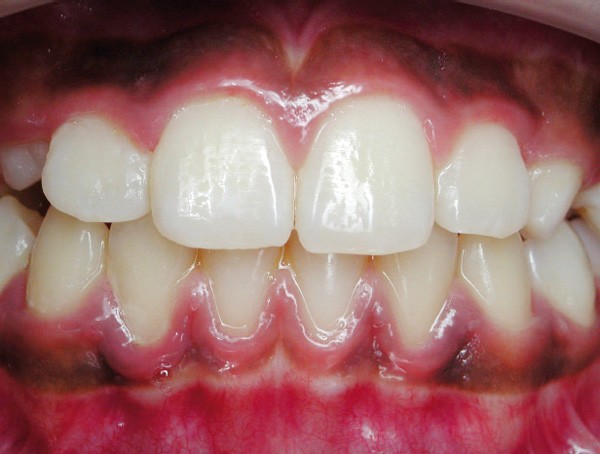

La parodontite chronique est une maladie inflammatoire d’origine bactérienne, dont la prévalence est très élevée. Bien que les progrès des thérapeutiques soient nombreux et concernent un nombre important de traitements parodontaux, la thérapeutique étiologique non chirurgicale reste le traitement initial de choix des parodontites. Elle comprend un enseignement à l’hygiène orale et un débridement mécanique du biofilm bactérien, à l’aide d’ultrasons ou de curettes. L’antibiothérapie systémique n’est pas systématique, mais est indiquée dans les cas les plus sévères. Souvent, la seule thérapie mécanique se montre efficace et suffisante pour obtenir des améliorations cliniques très significatives. Cependant, elle a aussi des limites, et certains sites d’accès délicats nécessitent alors une thérapeutique chirurgicale complémentaire. Enfin, la stabilisation de la situation à long terme ne peut être obtenue que si une maintenance rigoureuse et régulière est mise en place(fig. 5 et 6).